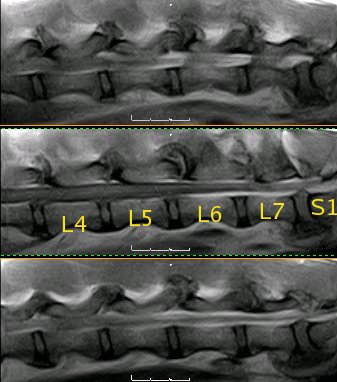

Resonancia magnética (SE T1 sagital) de la columna lumbar |

La médula espinal acaba en L5, donde empieza la cola de caballo |

Resonancia magnética lumbo-sacra de pastor alemán |